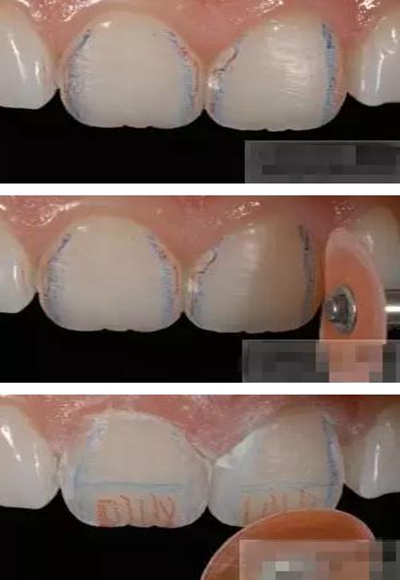

【分層堆塑】

A4本質(zhì)堆塑

Dr.Vanini建議如果牙醫(yī)選色有疑惑的話,最好應(yīng)用顏色深一些的牙本質(zhì)樹脂。

A3本質(zhì)堆塑

發(fā)育葉制作

白堊斑

切端琥珀色制作

A3頸部堆塑

涂布防氧化劑

充填初步完成

【初步修整】

對于唇面,首先使用火焰狀車針進行修整,一般不使用輪狀車針修整線角

微細的表面結(jié)構(gòu)最后使用鎢鋼拋光車針成形的。